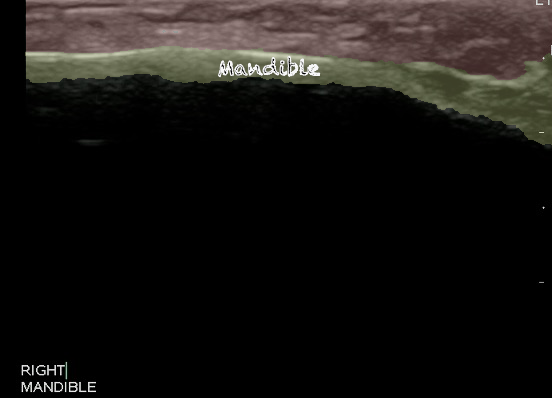

- Figure 5 and 6. Normal Mandible

- Bony structures like mandible, maxilla appear hyperechoic with a posterior hypoechoic acoustic shadow underneath.

- Fat has hyperechoic appearance on ultrasound.

- Muscles are generally visualized as hypoechoic structures but have a more heterogeneous striated appearance.

- Normal Mandible:

Video 4. Normal Mandible